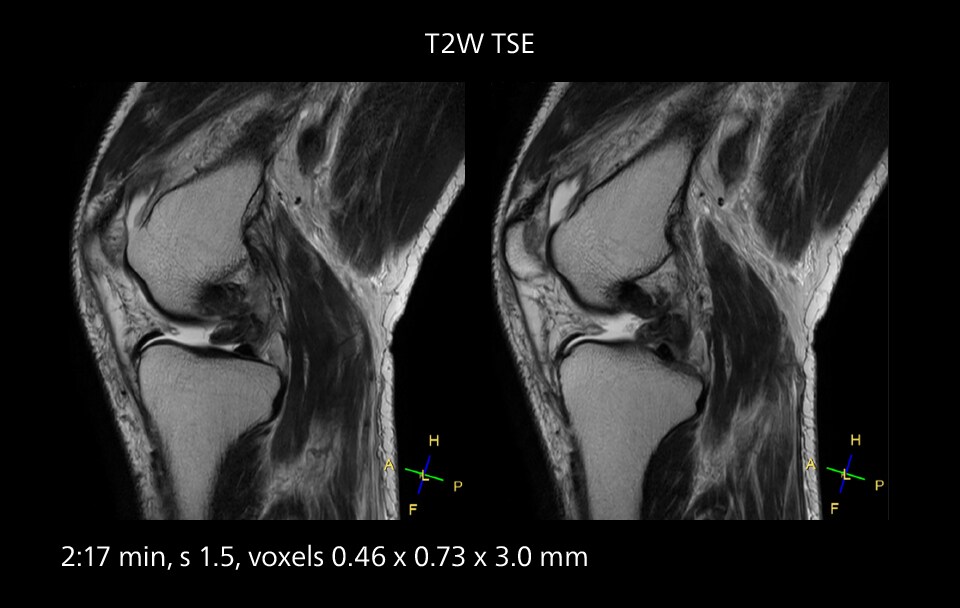

Images showing a posterior cruciate ligament (PCL) tear, a detached medial collateral ligament (MCL) on the tibial side and an intact anterior cruciate ligament (ACL). SmartPath to Elition X helped reduce scan time compared to previous imaging while maintaining resolution.

Sannodai Hospital radiologists had been very satisfied with their Ingenia 3.0T with Compressed SENSE, however after acquiring SmartPath to Elition X they have demonstrated improved image quality and even higher speeds in imaging studies throughout the body, according to Dr. Makuuchi. “Generally, we were impressed by seeing that images are very sharp and have higher SNR than we used to get with our Ingenia 3.0T system,” he notes. “We were delighted to see that high image quality can be obtained in a short time thanks to the Elition with its powerful An example of increased imaging speed is in knee studies. “There is a definite scan time reduction for T2* mFFE and proton density TSE – both of these sequences benefit from much shorter repetition times,” he reports.

gradients. Some high resolution examinations that were not possible before dueto their longer scan time, are now routinely performed with the upgraded system.”

Overall, imaging time per sequence has been reduced since the Elition X upgrade. This can help reduce the risk of patient movement and the need for rescans. “As our hospital has many elderly patients, we consider it important to obtain high-quality data in a short time,” Dr. Makuuchi says. “Shorter imaging times are also useful for accepting emergency patients, because faster emergency studies have a reduced impact on the daily examinations schedule. In emergency cases it is also important that high quality images are obtained in a short time.”